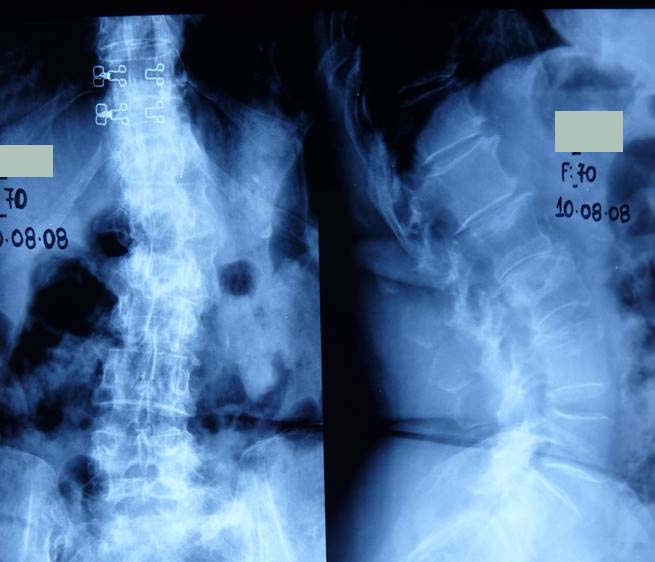

Εικόνα 1 (α, β, γ, δ)

1ος τύπος Εκφυλιστικού τύπου Σκολίωση (De Novo) εντοπιζόμενη στην οσφυϊκή περιοχή της  Σπονδυλικής Στήλης.

Στις ακτινογραφίες, (α)προσθιοπισθία και (β) πλαγία,  η πάσχουσα σε ηλικία 33 χρονών παρουσιάζει ελάχιστη σκολίωση, ενώ διατηρεί τη λόρδωση της.

Στις ακτινογραφίες  (γ) προσθιοπισθία και (δ) πλαγία, η ίδια σε ηλικία 50 χρονών παρουσιάζει σημαντικότατη σκολίωση της οσφυϊκής περιοχής, με παρεκτόπιση των σπονδύλων και οστεοαρθριτικές φθορές, επί πλέον δε έχει επέλθει και (δ) αναστροφή της λόρδωσης σε οσφυϊκή κύφωση. Οι μεταβολές αυτές είναι υπαίτιες για μεγάλο και συνεχή πόνο στην οσφυϊκή περιοχή και για έναρξη νευρολογικών διαταραχών στα κάτω άκρα.